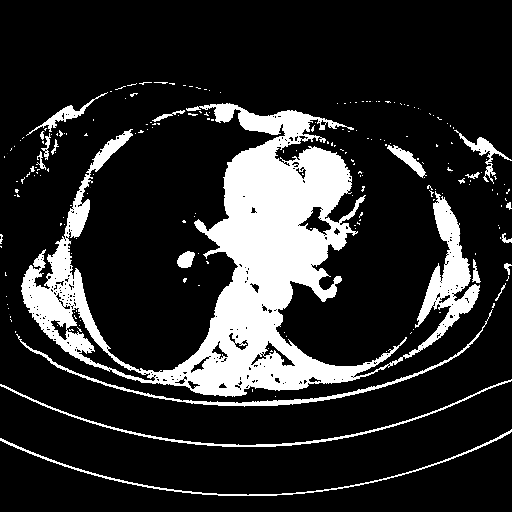

Original VENOUS CT scan

Full window (WL 1023.5, WW 4095 β†’ Low βˆ’1024, High +3071)

Actual HU range: [-1024.0, 3071.0]